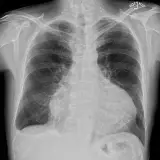

Over 2,100 interactive radiology cases, curated by radiologists for your level of training. Scroll, window, and view cases full screen — just like on PACS. Click linked findings in each writeup to jump straight to them on the image. Cases include sample reports, a focused discussion section, original illustrations, and videos.

完全交互式病例,配备您在 PACS 上期待的各项工具——滚动、调窗、缩放、平移、测量、ROI 和全屏模式。

丰富的标注直接在病例图像上突出关键发现。点击病例讲解中的关联发现,即可跳转至其在扫描上的精确位置。